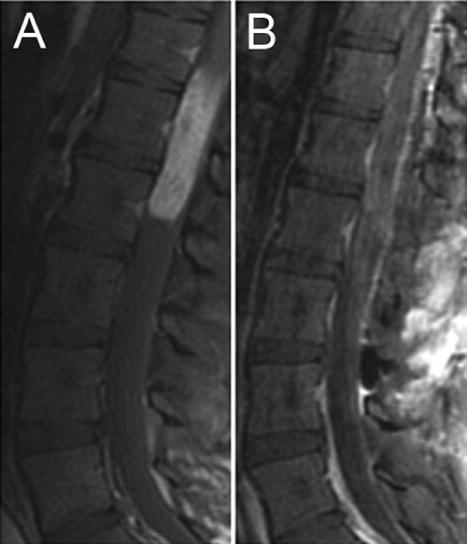

圖中患者患有脊柱2級(jí)(經(jīng)典)室管膜瘤的患者在對(duì)比劑給藥后矢狀前(A)和術(shù)后(B) T1加權(quán)MR圖像。這個(gè)3歲男孩到醫(yī)院外就診,經(jīng)歷了數(shù)周的疼痛和進(jìn)行性無(wú)力,使患者無(wú)法行走。頸椎的術(shù)前影像顯示頸髓內(nèi)有一個(gè)擴(kuò)張性髓內(nèi)病變,從顱骨向顱骨延展,從尾巴至T2–3(A)。病變表現(xiàn)出異質(zhì)性增強(qiáng),并出現(xiàn)在中心,而正常臍帶的邊緣位于周向?;颊呓邮芰嗽摬≡畹腟TR(B)。